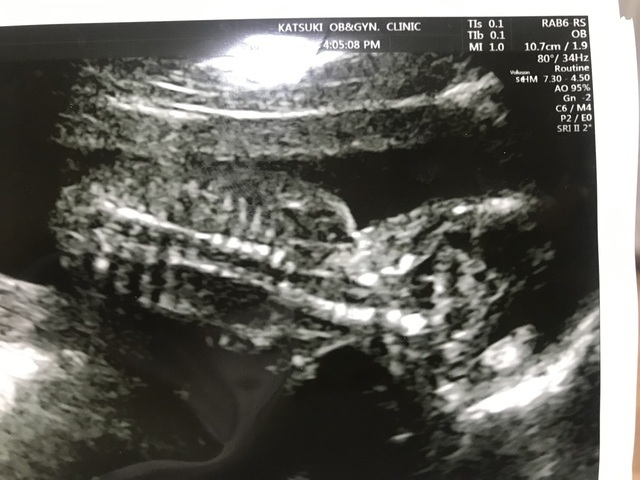

17週5日(17w5d・男の子)|ゆうち0809 さん(27歳)

エコー写真撮影時のエピソード:

健診に行くまでは、元気に成長しているかいつも不安でした。この頃はまだ胎動も感じていなかったので、健診で会えることがとても楽しみでした。このエコーを見たとには、背骨がしっかりしていてびっくりしました!お腹に中にいる小さい赤ちゃんですが、骨組みもしっかりしてきて、立派な人間なんだなあと思った写真でした。